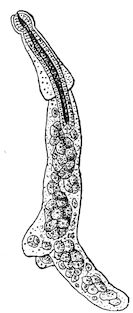

Fig. 1.—Rachitis in a young goat.

Fig. 1.—Rachitis in a young goat.